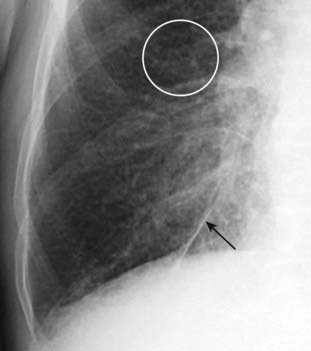

Figure 9-11 Kerley A lines.

The A lines (circle) appear when connective tissue near the bronchoarterial bundle distends with fluid. They extend from the hila for several centimeters in the midlung and do not reach the periphery of the lung like Kerley B lines do. A network of Kerley lines is produced in the lungs in patients with congestive heart failure producing the “prominence of the pulmonary interstitial markings” seen in that disease.